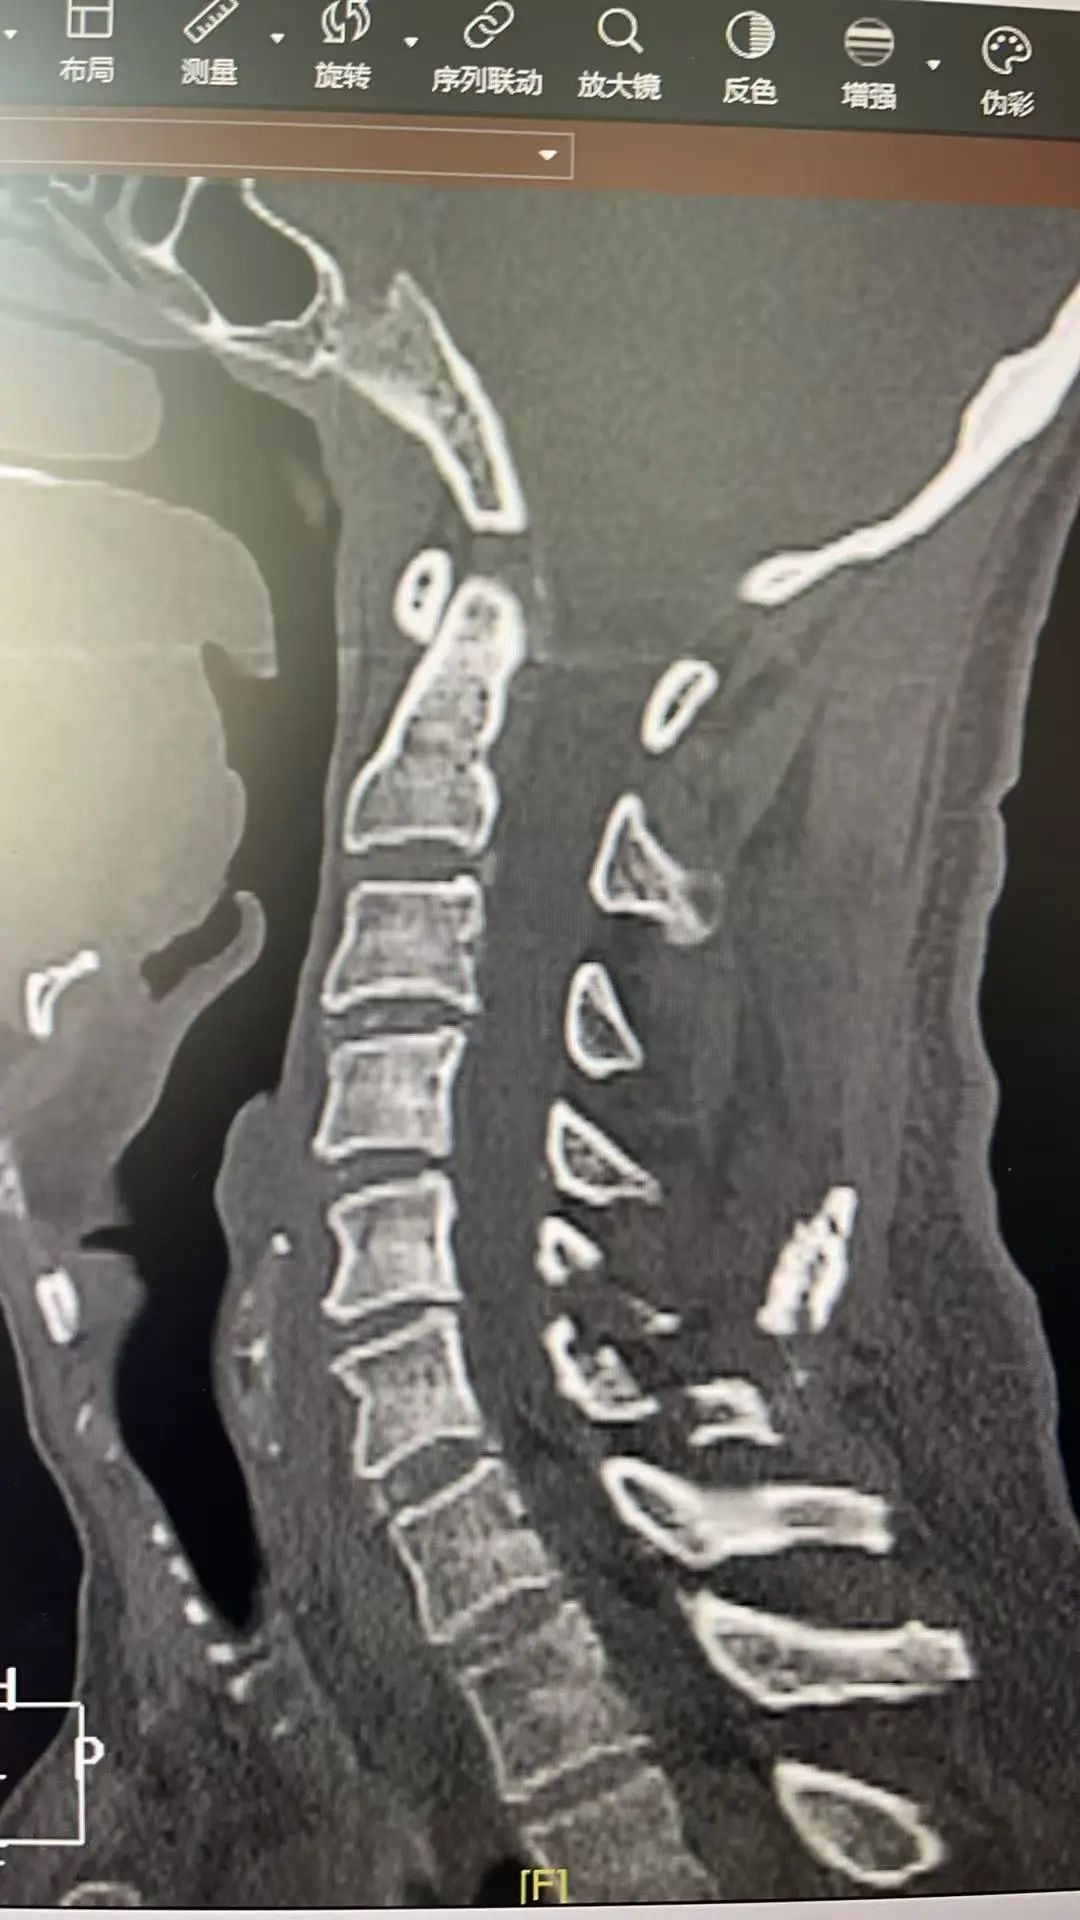

▲术前CT影像

为求治疗,陈伯在家属陪同下来到茂名市人民医院脊柱外二科赵斌修主任医师专家门诊就诊,经详细询问病史与查体,陈伯被确诊为“C5/6右侧黄韧带骨化合并颈椎管狭窄/脊髓半切综合征(不典型)”,急需住院手术治疗,否则若病情继续发展,病人终会因脊髓逐渐受压加重而出现瘫痪。从影像学检查来看,病人颈椎黄韧带钙化灶压迫较大,横截面上已占据相当大的面积,挤压颈髓严重,手术风险极大;赵斌修主任医师坦言:“这类病例若采用以前传统的开放手术,需大范围切开椎板,创伤大、出血多、恢复慢、手术道口容易感染,而且治疗花费大,术中如果稍有不慎可能损伤脊髓,导致病人截瘫的不可逆后果” 。赵斌修主任医师团队反复研讨,最终决定采用当今国际前沿的单侧双通道脊柱内镜技术(UBE)为病人行手术治疗。